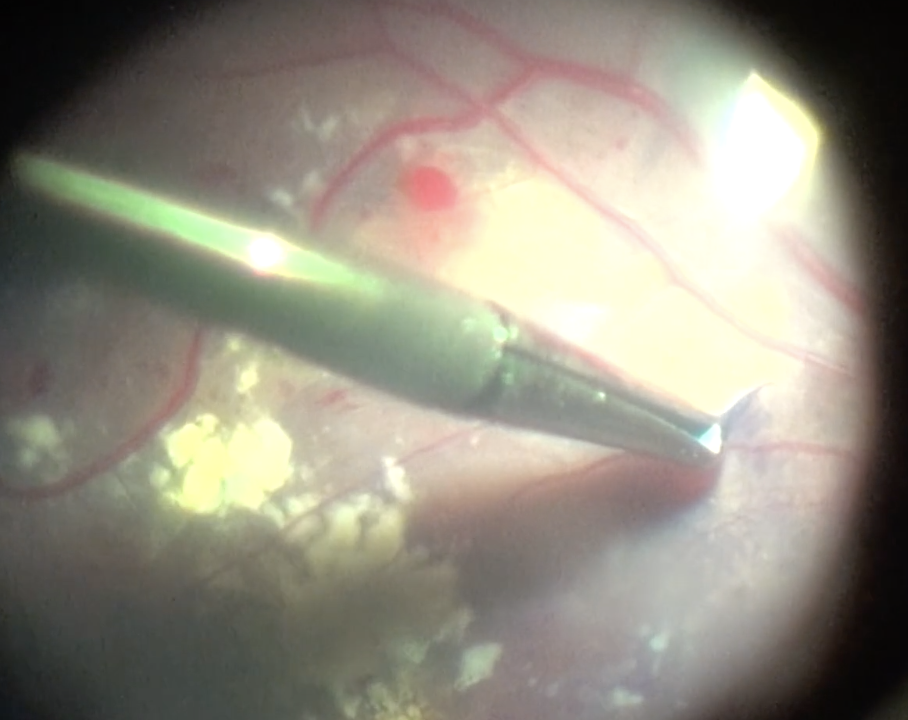

Surgical Pearl Video

Pearls for righting aqueous misdirection

How to do a pars plana vitrectomy with irido-zonulo-hyaloidectomy when laser and medical therapy fail.